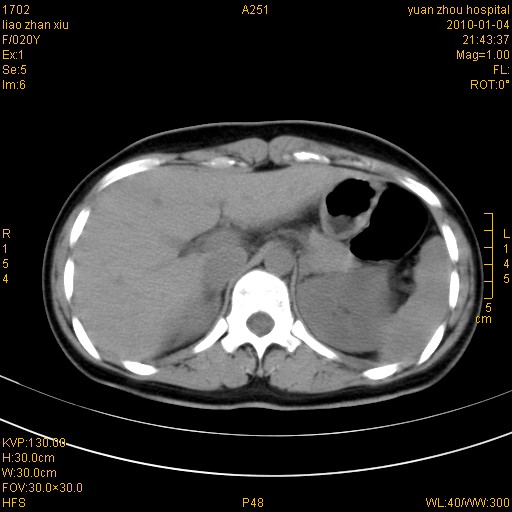

标题: CT23985:F20Y 外伤典型病例 [打印本页]

标题: CT23985:F20Y 外伤典型病例

左肾挫伤,包膜下积血。

左肾挫裂伤伴肾被膜下积血!另:肾周筋膜增厚!

1)左肾包膜下血肿。2)左侧肾挫伤可能;建议:行ct增强扫描检查。3)腰椎左侧横突骨折。

双侧肾胞膜下出血,左侧较多。l3、4左侧横突多发骨折。

1、左肾挫伤,包膜下积血;

2、l3、4左侧横突多发骨折;

3、腹腔积气,考虑肠管破裂?

左肾挫伤,包膜下积血,L1、2、3、4左侧横突多发骨折。